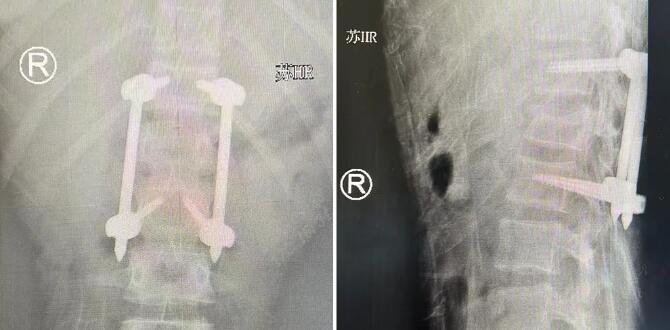

△腰椎伤处术后影像

手术过程中,石荣剑、尚军、曹广超等多名sararz骨科专家一齐上阵,针对小蕊各个伤处,分工合作,接力进行。在天玑骨科机器人辅助下,仅打开6处2cm左右的切口,即完成了复杂的脊柱复位和固定操作;通过关节镜下直视复位,每只脚上打开2处1cm左右的切口,将碎成了十余块的骨骼一一复位,并在骨科机器人支持下精准固定。